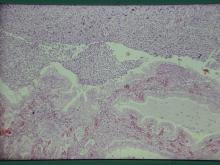

子宮體及子宮角明顯膨大,尤其靠兩側子宮角之前1/2段膨大更為明顯(圖5),子宮角切開可見血樣、膿樣分泌物,子宮壁明顯變薄,子宮內膜表面瀰漫散佈點狀火山口樣之潰瘍灶(圖6),子宮重量4.2公斤。 三、 組織病變: 病例一:

子宮腔及子宮黏膜腺體腔內蓄積大量粘液及膿性滲出物(圖3),子宮內膜覆蓋

上皮受損處,其上皮下層之間質組織有顯著的炎症反應。(圖4)病例二: